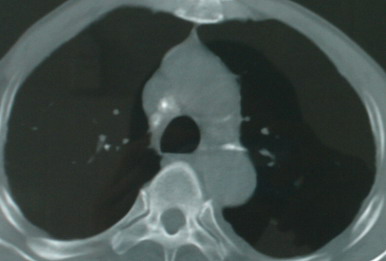

以下是引用医影拾贝在2008-6-3 18:48:00的发言:[br]双上肺弥漫性小结节影,纵隔窗内钙化淋巴结影,考虑血播性tb可能性较大,不除外肺ca可能

以下是引用卜一在2008-6-3 19:33:00的发言:[br]双肺结节,以双上肺分布为多,期间搀杂片状致密影及索条致密影。考虑:继发性肺结核伴血型播散可能性大。不除外肺泡ca的可能!另:椎体退变!

以下是引用panyishengct在2008-6-3 21:09:00的发言:[br]双上肺弥漫性小结节影,纵隔窗内钙化淋巴结影,考虑矽肺或/和tb可能性较大,不除外肺ca可能。腰椎考虑退变。 [br][br]